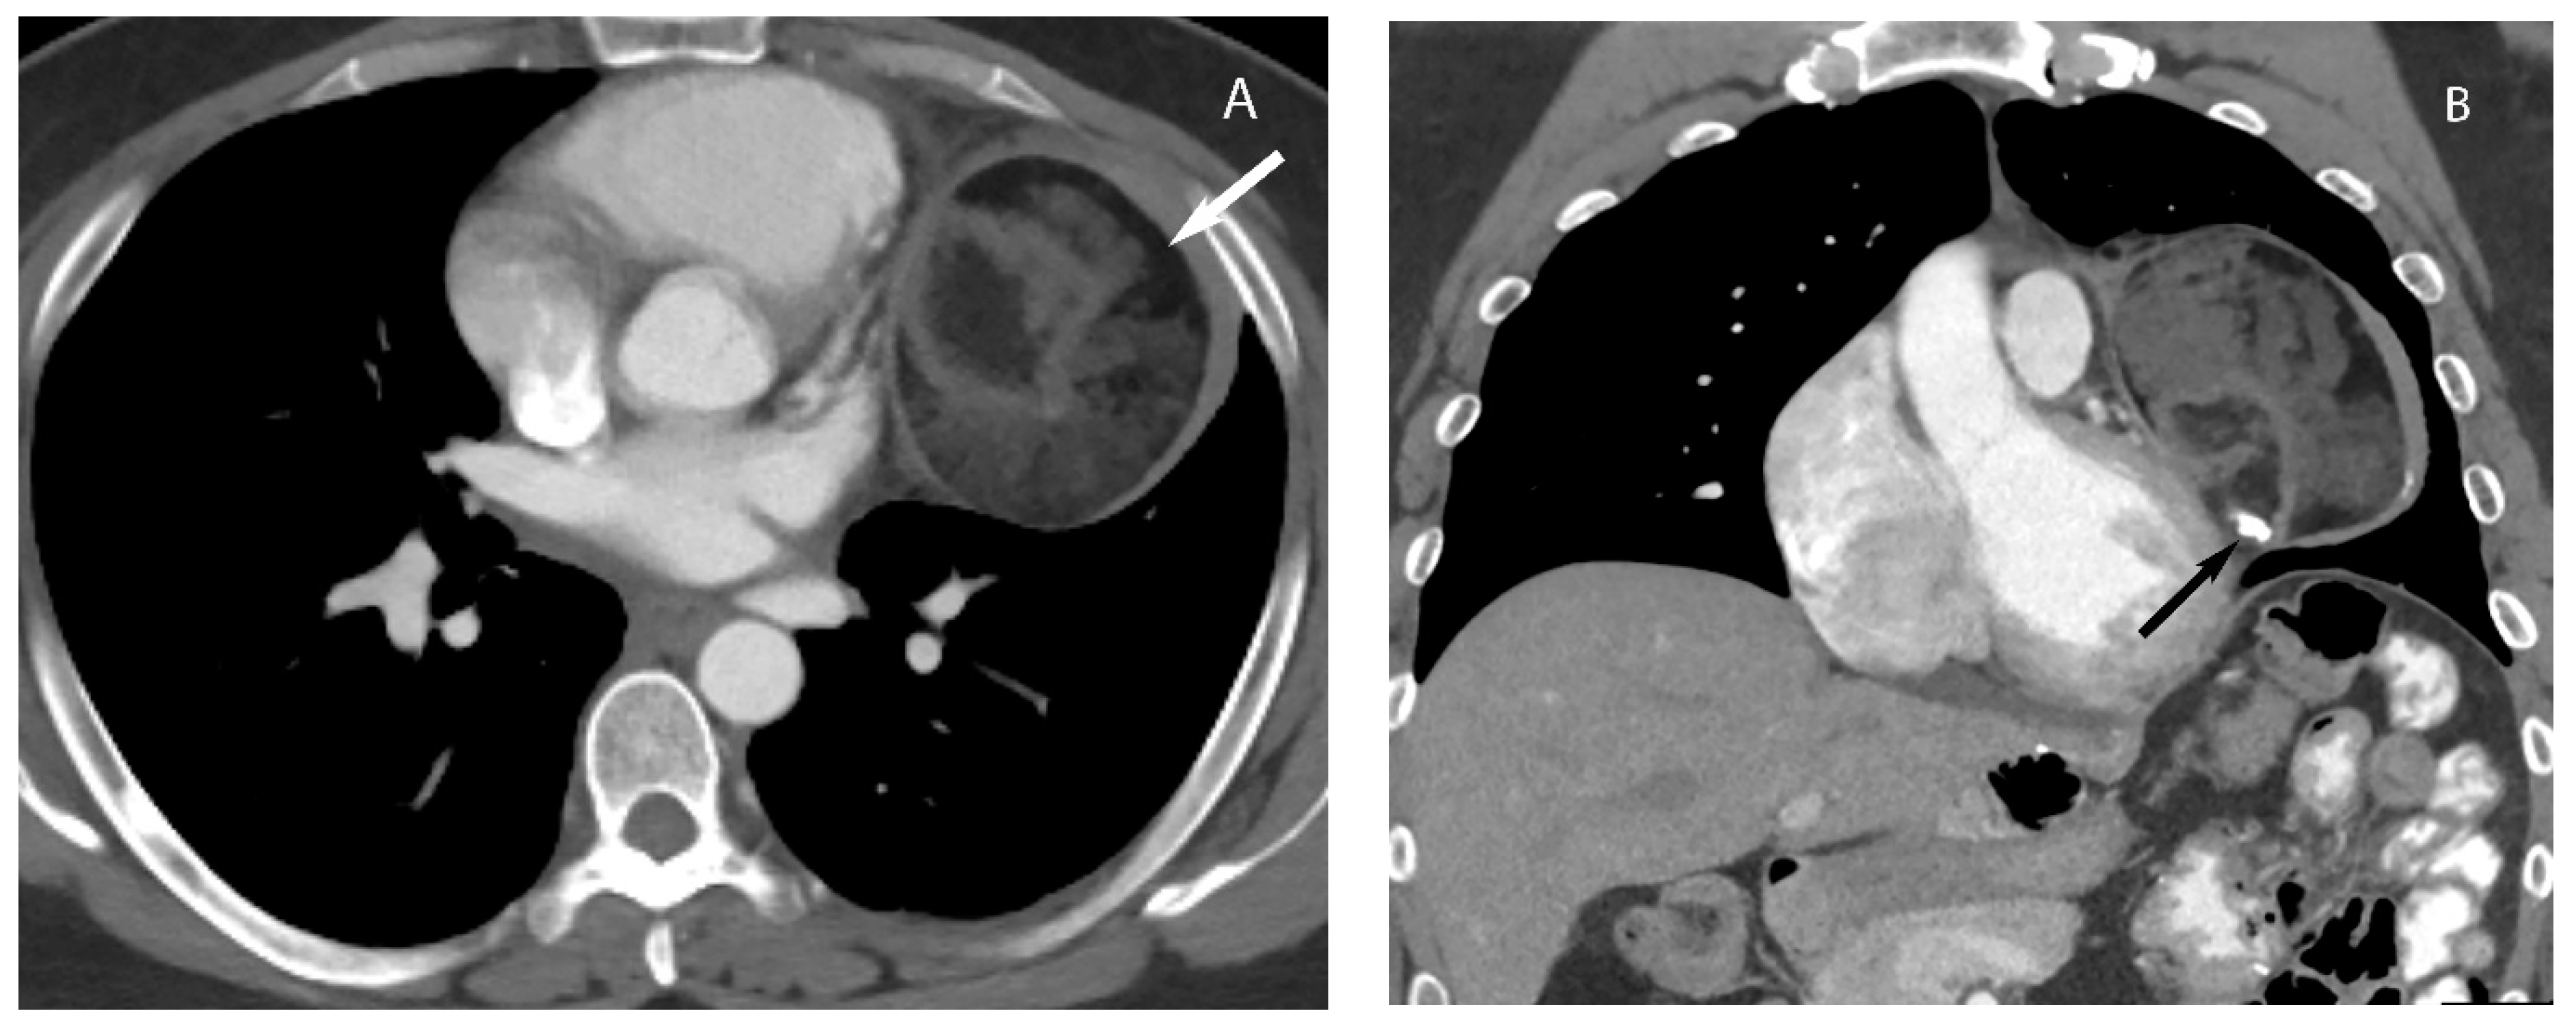

5. Thymic Epithelial Neoplasms

Visceral (Middle) Compartment